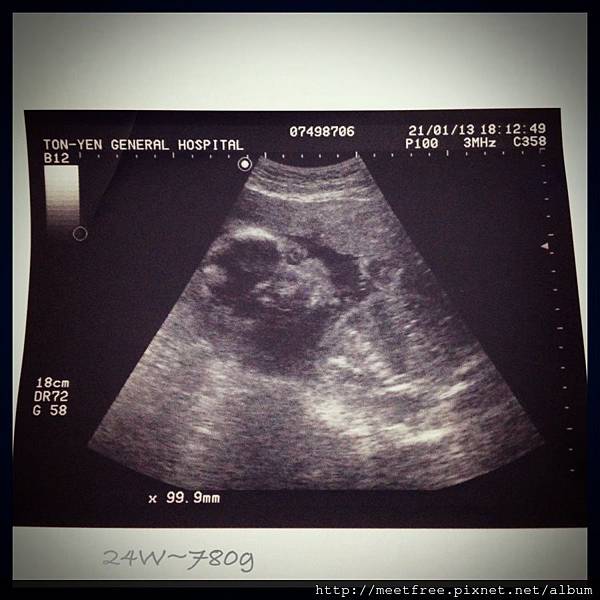

• 【媽咪日記】-滿24W,邁入中後期囉

24W2013/01/21 Mon.(一)

今天小妞很給面子,一開始就側面對著我們,

看到眼窩,鼻子,嘴唇,下巴還有長肉的小臉頰,

雖然爸拔跟媽咪是有看沒有懂,

(繼續閱讀...)